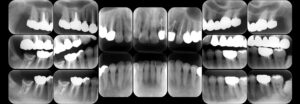

デンタルX線写真

デンタルX線写真は、歯の一部分を詳しく確認するためのものです。

口の中に小さなフィルムを入れて狭い範囲を撮影することで、歯間の小さな虫歯や、歯の根の先端部分の異常など、細かい部分まで確認できます。

特定の部位の状態を詳しく知りたい場合に使われ、パノラマX線写真よりも詳細な情報を得られる点が特徴です。